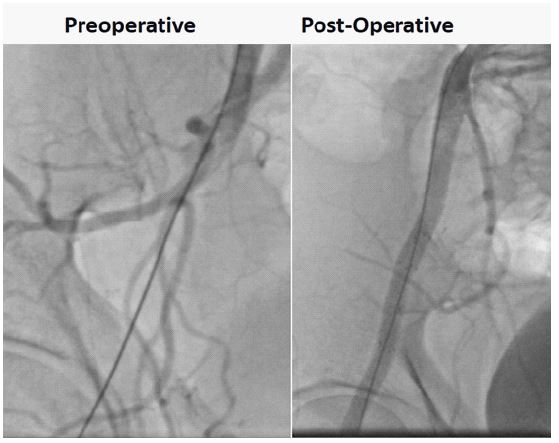

A male patient, 59 years old, with arterial hypertension, ischemic heart disease, active smoker was admitted with left inferior limb disabling claudication. AngioCT-Scan showed distal aorta and complete left iliac common and external artery occlusion. The patient was submitted to left femoral common artery endarterectomy and profundoplasty followed by complete recanalization of the left iliac common and external artery occlusion with Wrapsody 8×125 mm and 7×75 mm respectively. (Figure 6). The patient was discharged from the hospital second day post-operative and 1-month follow-up showed endoprosthesis patency with complete resolution of the previous symptoms.

Figure 6: Left Femoral common artery endarterectomy and profundoplasty followed by complete recanalization of the left iliac common and external artery occlusion with Wrapsody 8×125 mm and 7×75 mm respectively.